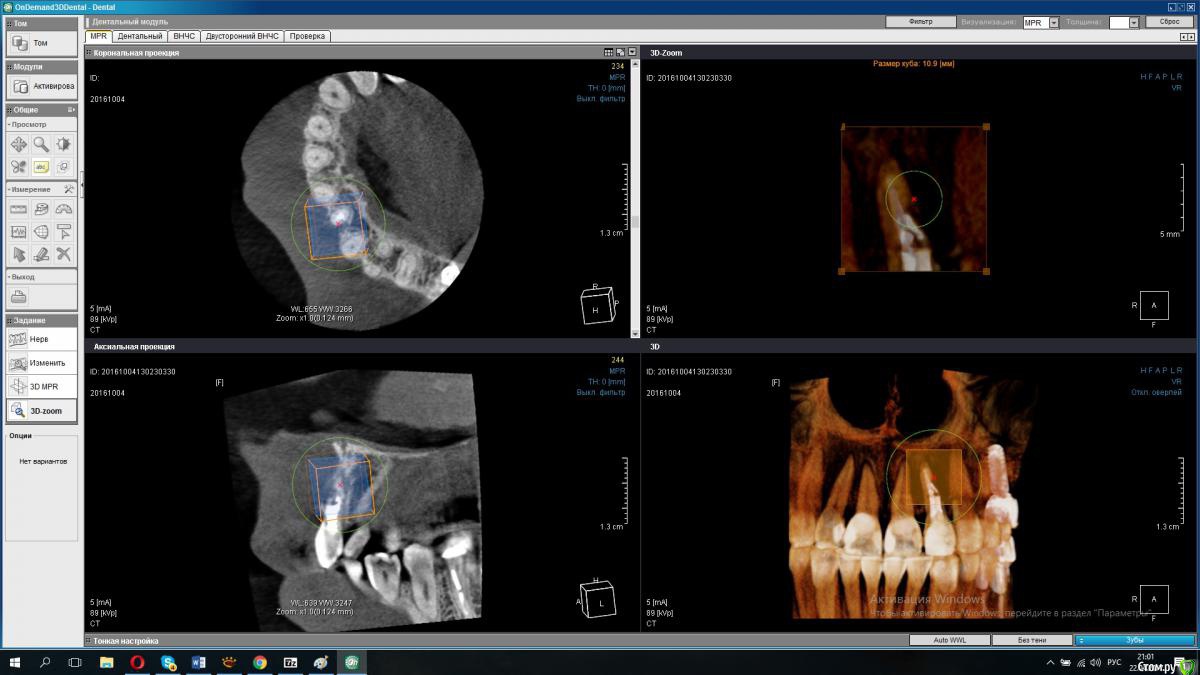

Lanasvlisa Опубликовано 21 апреля, 2017 Поделиться Опубликовано 21 апреля, 2017 Добрый вечер, уважаемые врачи! Вопрос по зубу 22, он леченый-перелеченный, сейчас на корне обнаружена киста, на десне над зубом свищевой ход. Какое ваше мнение: 1) удалять зуб и вместе с ним уйдет воспаление, прочищать все и заниматься имплантацией; или 2) можно каким-то образом удалить кисту, отсечь корень (читала о таком), но сам зуб не удалять? Если всё-таки 1), то можно ли осуществить в данном случае одномоментную имплантацию с нагрузкой? или можно одномоментную, но без нагрузки...? Спасибо огромное всем, кто посмотрит снимки и выразит свое экспертное мнение! С уважением, PS: прикрепляю скриншот из программы, но если этого недостаточно для определения диагноза и плана вмешательства, то скину ссылку на весь архив. Ссылка на комментарий

Bier Опубликовано 21 апреля, 2017 Поделиться Опубликовано 21 апреля, 2017 3д реконструкция нам не подходит. Хотя по ней все довольно печально выглядит.покажите скриншоты срезов. Ссылка на комментарий

колесников Опубликовано 21 апреля, 2017 Поделиться Опубликовано 21 апреля, 2017 Резецировать там нечего,во время эндодонтического лечения произошла перфорация стенки корня зуба,вокруг этого участка очаг деструкции костной ткани. Это не лечится.По выставленной вами картинке объём деструкции не понятен. Решить возможность одномоментной имплантации и тем более немедленной нагрузки может только ваш лечащий доктор ,по результатам кт и в соответствии со своим опытом. Ссылка на комментарий

Lanasvlisa Опубликовано 22 апреля, 2017 Автор Поделиться Опубликовано 22 апреля, 2017 Здравствуйте, уважаемые врачи, и спасибо большое вам за оперативные ответы! Я не знаю, как найти срезы, полагаю, проекции - это то же самое, что и срезы? Я сделала их скриншоты+ еще три фото. А если я все-таки отправлю ссылку на весь архив, вы бы могли оценить объем разрушения костной ткани, чтобы предположить, насколько реально провести имплантацию в день удаления? У меня еще такие вопросы: если имплантацию удается провести сразу, то 1) через какой срок можно в моем случае заняться установкой коронки; 2) какая она должна быть; 3) если придется пользоваться "бабочкой" (я так понимаю, это единственный вариант, все временные коронки, в том числе клеевые, - это нагрузка, а каппа сюда тоже не подойдет?), то как потом происходит восстановление формы десны? Можно ли как-то сохранить десневые сосочки в случае отсроченной имплантации? Спасибо большое! Ссылка на комментарий